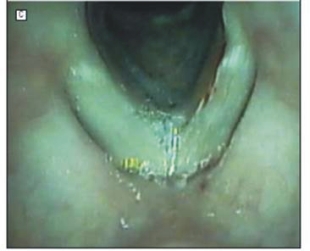

圖三、手術不僅出血量甚小,且治療後即可恢復平整之聲帶外觀